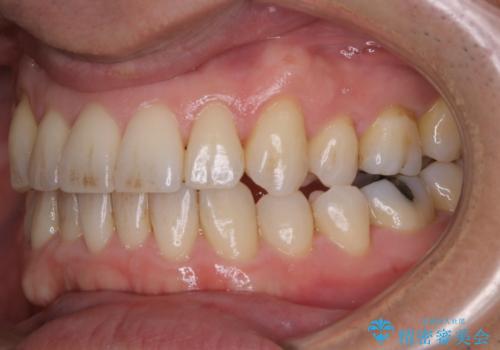

- メンテナンスの際に歯のステインが気になるということで今回はエアフローの機械を使用したクリーニングを行いました。

ステインが付着したままだと歯の表面がざらつき、普段のブラッシング時などに汚れが落ちにくくなります。定期的なメンテナンスの際にPMTC、エアフローを取り入れることをおすすめしております。